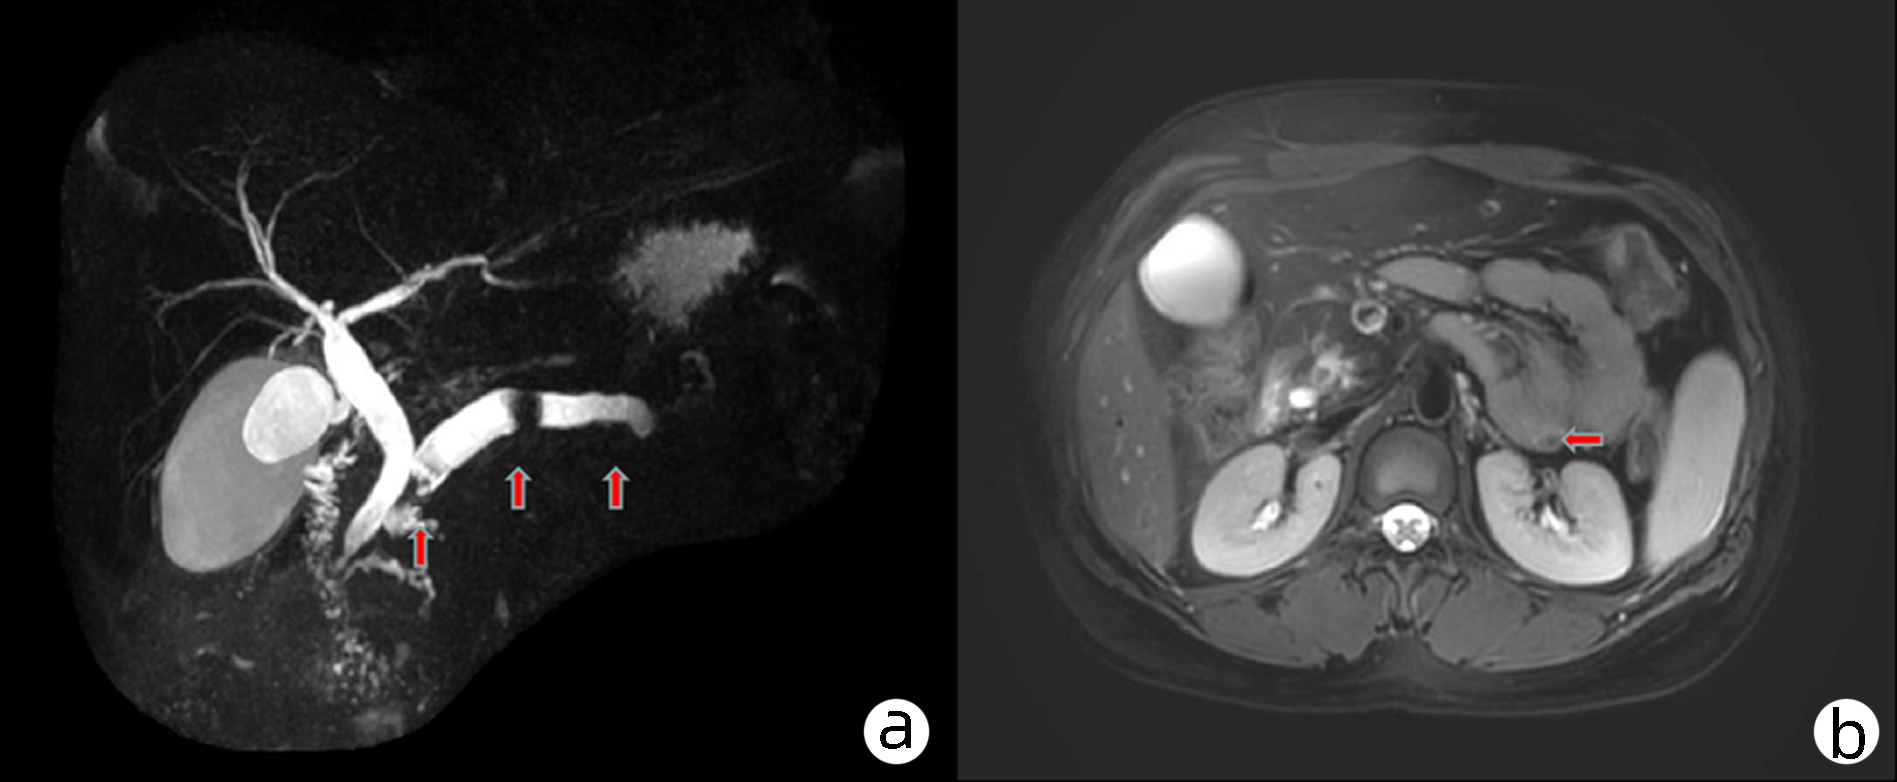

阿卜杜萨拉木·图尔荪麦麦提, 张云飞, 姚刚, 沙地克·阿帕尔, 吐尔洪江·吐逊, 温浩

2023, 39(8): 1922-1925. DOI: 10.3969/j.issn.1001-5256.2023.08.023

摘要(1461) HTML (312) PDF (2217KB)(118)

摘要:

遗传性球型红细胞增多症是一种人体红细胞膜缺陷遗传性溶血疾病,主要以贫血、黄疸、脾大为主要症状,因临床症状不典型,容易误诊漏诊,目前临床上总胆红素及直接胆红素极高病例较少见,国内外很少有报道,文本患者入院接受治疗时总胆红素高达1 686.01 μmol/L,直接胆红素高达1 166.6 μmol/L。经外科治疗该患者顺利出院,术后随访一般情况佳,生活质量高,本文总结了外科治疗遗传性球型红细胞增多症的相关诊疗经验。